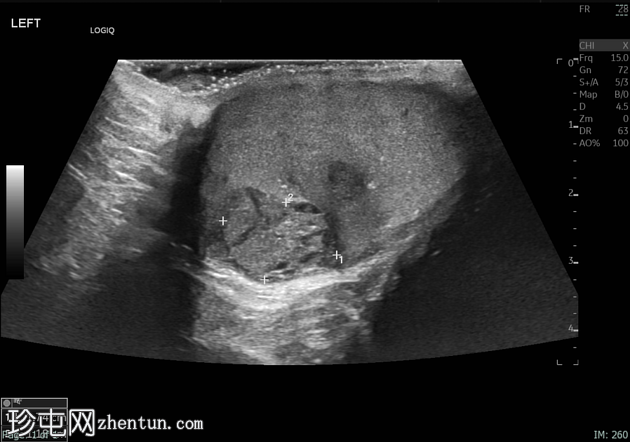

睾丸混合性生殖细胞瘤

左侧睾丸无痛性肿胀2个月。

年龄:20岁

性别:男

超声检查

纵切面

左侧睾丸肿大,体积约56 mL,可见弥漫性微结石,以及三个内部等回声病灶,伴囊性变、微钙化和明显血流信号,最大病灶大小约4.8 x 3.2 cm。

未见腹主动脉旁或髂淋巴结肿大。